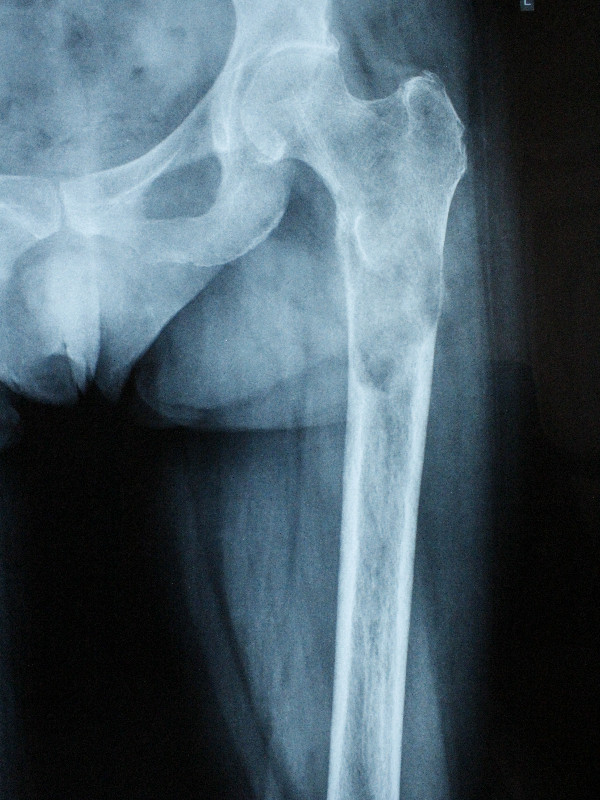

1 . ՌԴ-ում երկրորդային բնույթի կոտրվածքի ֆիքսացիա իրականացնելուց հետո՝ 40-ամյա բուժառուն դիմել է «Նաիրի» ԲԿ։ Բուժառուի մոտ ախտորոշվել է ոսկրային պլազմոցիտոմա։ Քիմոթերապիա ստանալուց հետո՝ 40-ամյա բուժառուն վիրահատվել է։ Կոնք-ազդրային հոդի հետ միասին հեռացվել է ազդրոսկրի վերին երրորդականը։ Առաջացած դեֆորմացիան շտկվել է էնդոպրոթեզով: «Նաիրի» ԲԿ-ի փորձառու թիմի և պրոֆեսիոնալ մոտեցման շնորհիվ՝ հաջողվել է պահպանել բուժառուի գործող վերջույթը։

Վիրահատությունից առաջ